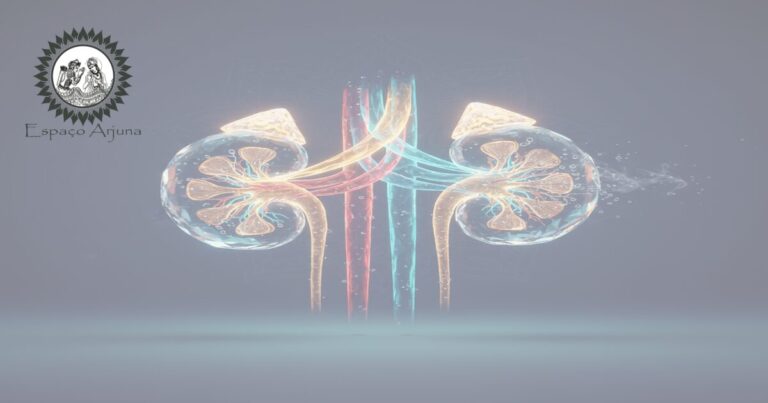

Visão clínico-científica sobre lesão renal aguda (LRA): causas, fatores de risco, sinais, diagnóstico, tratamento, prevenção e integração com práticas complementares.